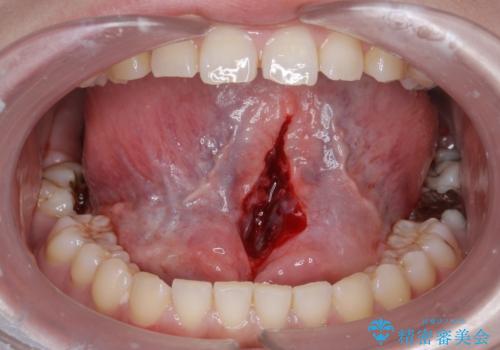

- 舌小帯を切りたいとの事で来院。

麻酔を行い、舌小帯切除術を行いました。

舌の可動域が広がりました。